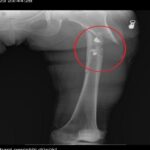

Yaraladığı sevgilisi Fatma O.’yu da 8 kurşunla yaralayan Sarıkaya, daha sonra arkadaşının cansız bedenini çarşafa sararak gizledi. Yaralı durumda olan Fatma O.’ya, 21 gün boyunca cinsel saldırıda bulunduğu belirtiliyor.